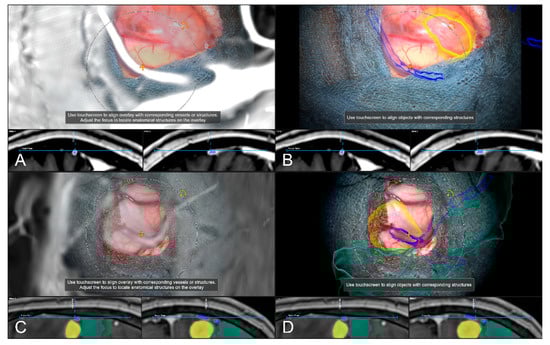

Alternative to bony and/or vascular landmarks, in 40 cases (13.65%) a cortex representation gained by automatic segmentation of cranial structures was used to evaluate and verify navigational accuracy. As the in-plane object representation is not straightforward, the Overview View was used firsthand in all cases to evaluate navigation accuracy allowing for superimposing the microscope video on the 3D visualization of the segmented data, see Figure 9. If a mismatch was seen, switching to the navigation update feature allowed for an in-plane transformation of the date to overcome the seen misalignment in the focus plane. This was the case in two patients (5.00%), whereas in the remaining 38 cases (95.00%), there was no need for further alignments was seen. In both cases, a linear transformation by on average 5.31 ± 1.57 mm and 1.75° ± 2.47° led to sufficient accuracy.

Figure 9.

Superimposing the microscope video on the 3D visualization of patient MRI data including the pre-segmented objects (cerebrum and tumor) intuitively relating video frame and 3D anatomy (upper part in A–D), in parallel view of AR-supported microscope view, probe’s eye view and target view (bottom part in A–D from left to right). Moving the focus plane (superimposed microscope video) along the optical axis of the microscope (A–D), the registration quality can be evaluated showing a sufficient match in this case.